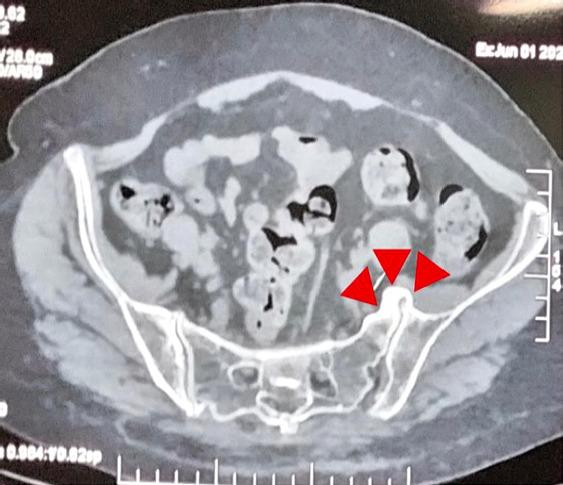

A 60-year-old female patient with grade 2 L5-S1 lytic listhesis initially underwent lumbar interbody fusion to address chronic low back pain and radiculopathy, resulting in significant symptom resolution for a brief period. The patient experienced a resurgence of symptoms within a short duration that proved refractory to conventional medical management and interventional pain management procedures. Ultimately, the patient achieved sustained relief after undergoing endoscopic SIJ ablation.

一名60岁女性患者,患有2级L5-S1溶解性椎体滑脱,最初接受了腰椎椎间融合术以解决慢性腰痛和神经根病,短期内症状得到了显著缓解。患者在短时间内症状复发,事实证明对传统药物治疗和介入性疼痛管理程序均无效。最终,患者在接受内镜下骶髂关节消融术后实现了持续缓解。